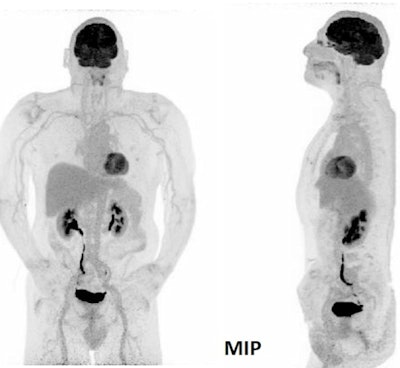

The team also imaged a neuroendocrine tumor in a two-minute acquisition scan. "Image quality is very nicely preserved," he said.

New PET/CT equipment is also useful when imaging in non-optimal conditions, for example, patients with adipose tissues or a non-optimal blood glucose level.

"For these patients, this might be a real game changer," said Rominger, who presented the case of an 87-year-old obese patient with adenocarcinoma of esophagogastric junction (AEG) and a heavily increased blood glucose level. "We could image this patient to a certain extent and see the hypermetabolic lesion quite easily in less than two minutes."

Non-optimal conditions with elevated blood glucose level and obesity (adenocarcinoma AEG, BG: 12.3 mmol/l, BMI 32kg/m2, 3 MBq/kg FDG, 60 min p.i, 6 min acquisition).The new system also enables further dose reduction. Researchers found out that even frames as short as ten seconds comply with current European Association of Nuclear Medicine (EANM) Research Ltd. (EARL) guidelines for the standardization of PET imaging developed for conventional systems.